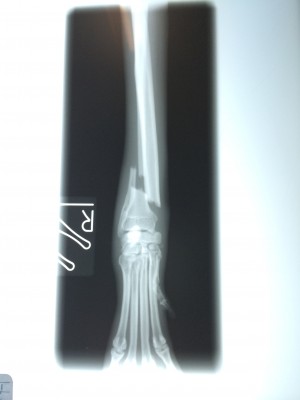

でもこれにも先生から説明があり『今回の手術はギブス固定ではなく、プレート2枚を使いしっかり固定をしているのでギブスは必要ありません。ギブスをしてしまうと、血流が悪くなること、自宅で患部の状況が解らないこと、骨折した足をほとんど使わないケースがあり筋肉が弱くなることもあるので必要なけでば使用しません』

そして詳しい手術経過の説明をして下さいました。今回の骨折は関節に近い部分であった為、より固定を安定させる為にプレートを2枚にしました。レントゲン写真を見ながら説明をして下さいました。(もちろん写真撮影は先生に許可を頂いてから行っています)

レントゲン写真を観た時は本当に可哀想になりました。。。痛かったね。。。